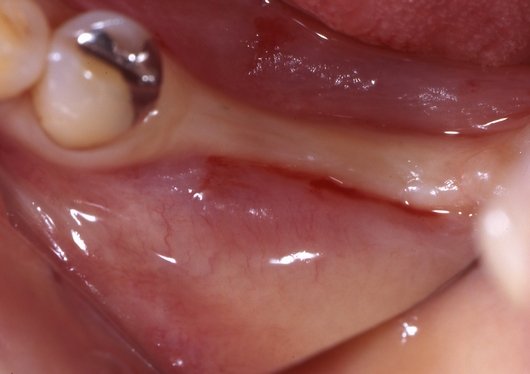

インプラント治療途中

抜歯後何年も経過されており、骨が痩せていたため骨造成手術の後にインプラント埋入を行いました。診査時に咬み合わせから考慮し、ポジションを見極める事で、等間隔にインプラントが埋入されています。